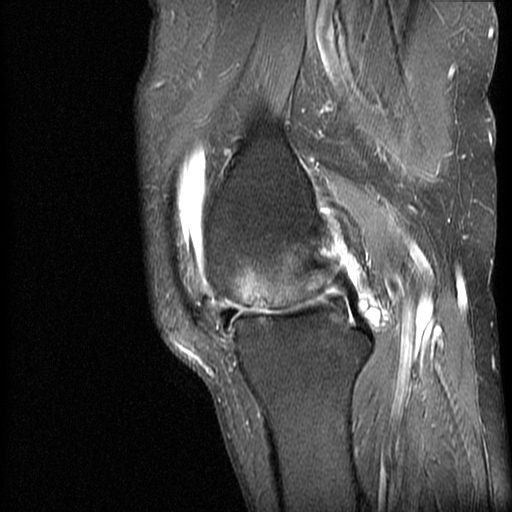

Cysts and Bursae

Large Baker's Cyst with PVNS